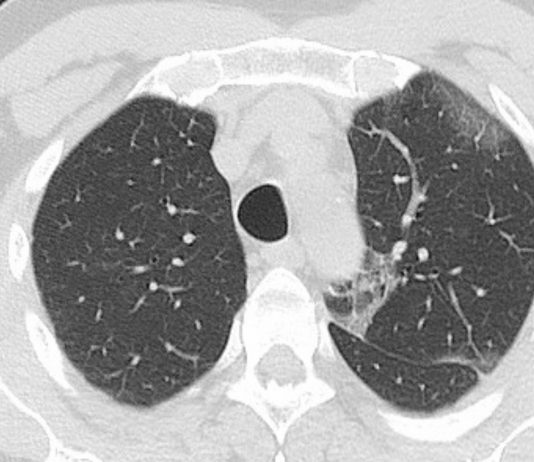

Filippo Barbiera - ASP Agrigento Presidio Ospedaliero di Sciacca (AG)

48-year-old female

MD with cough since February 29 and RT-PCR test positive. Blood test:

leukopenia.

Potential risk for SARS-CoV-2 exposure (one contact coming from “high-risk” area)

CT